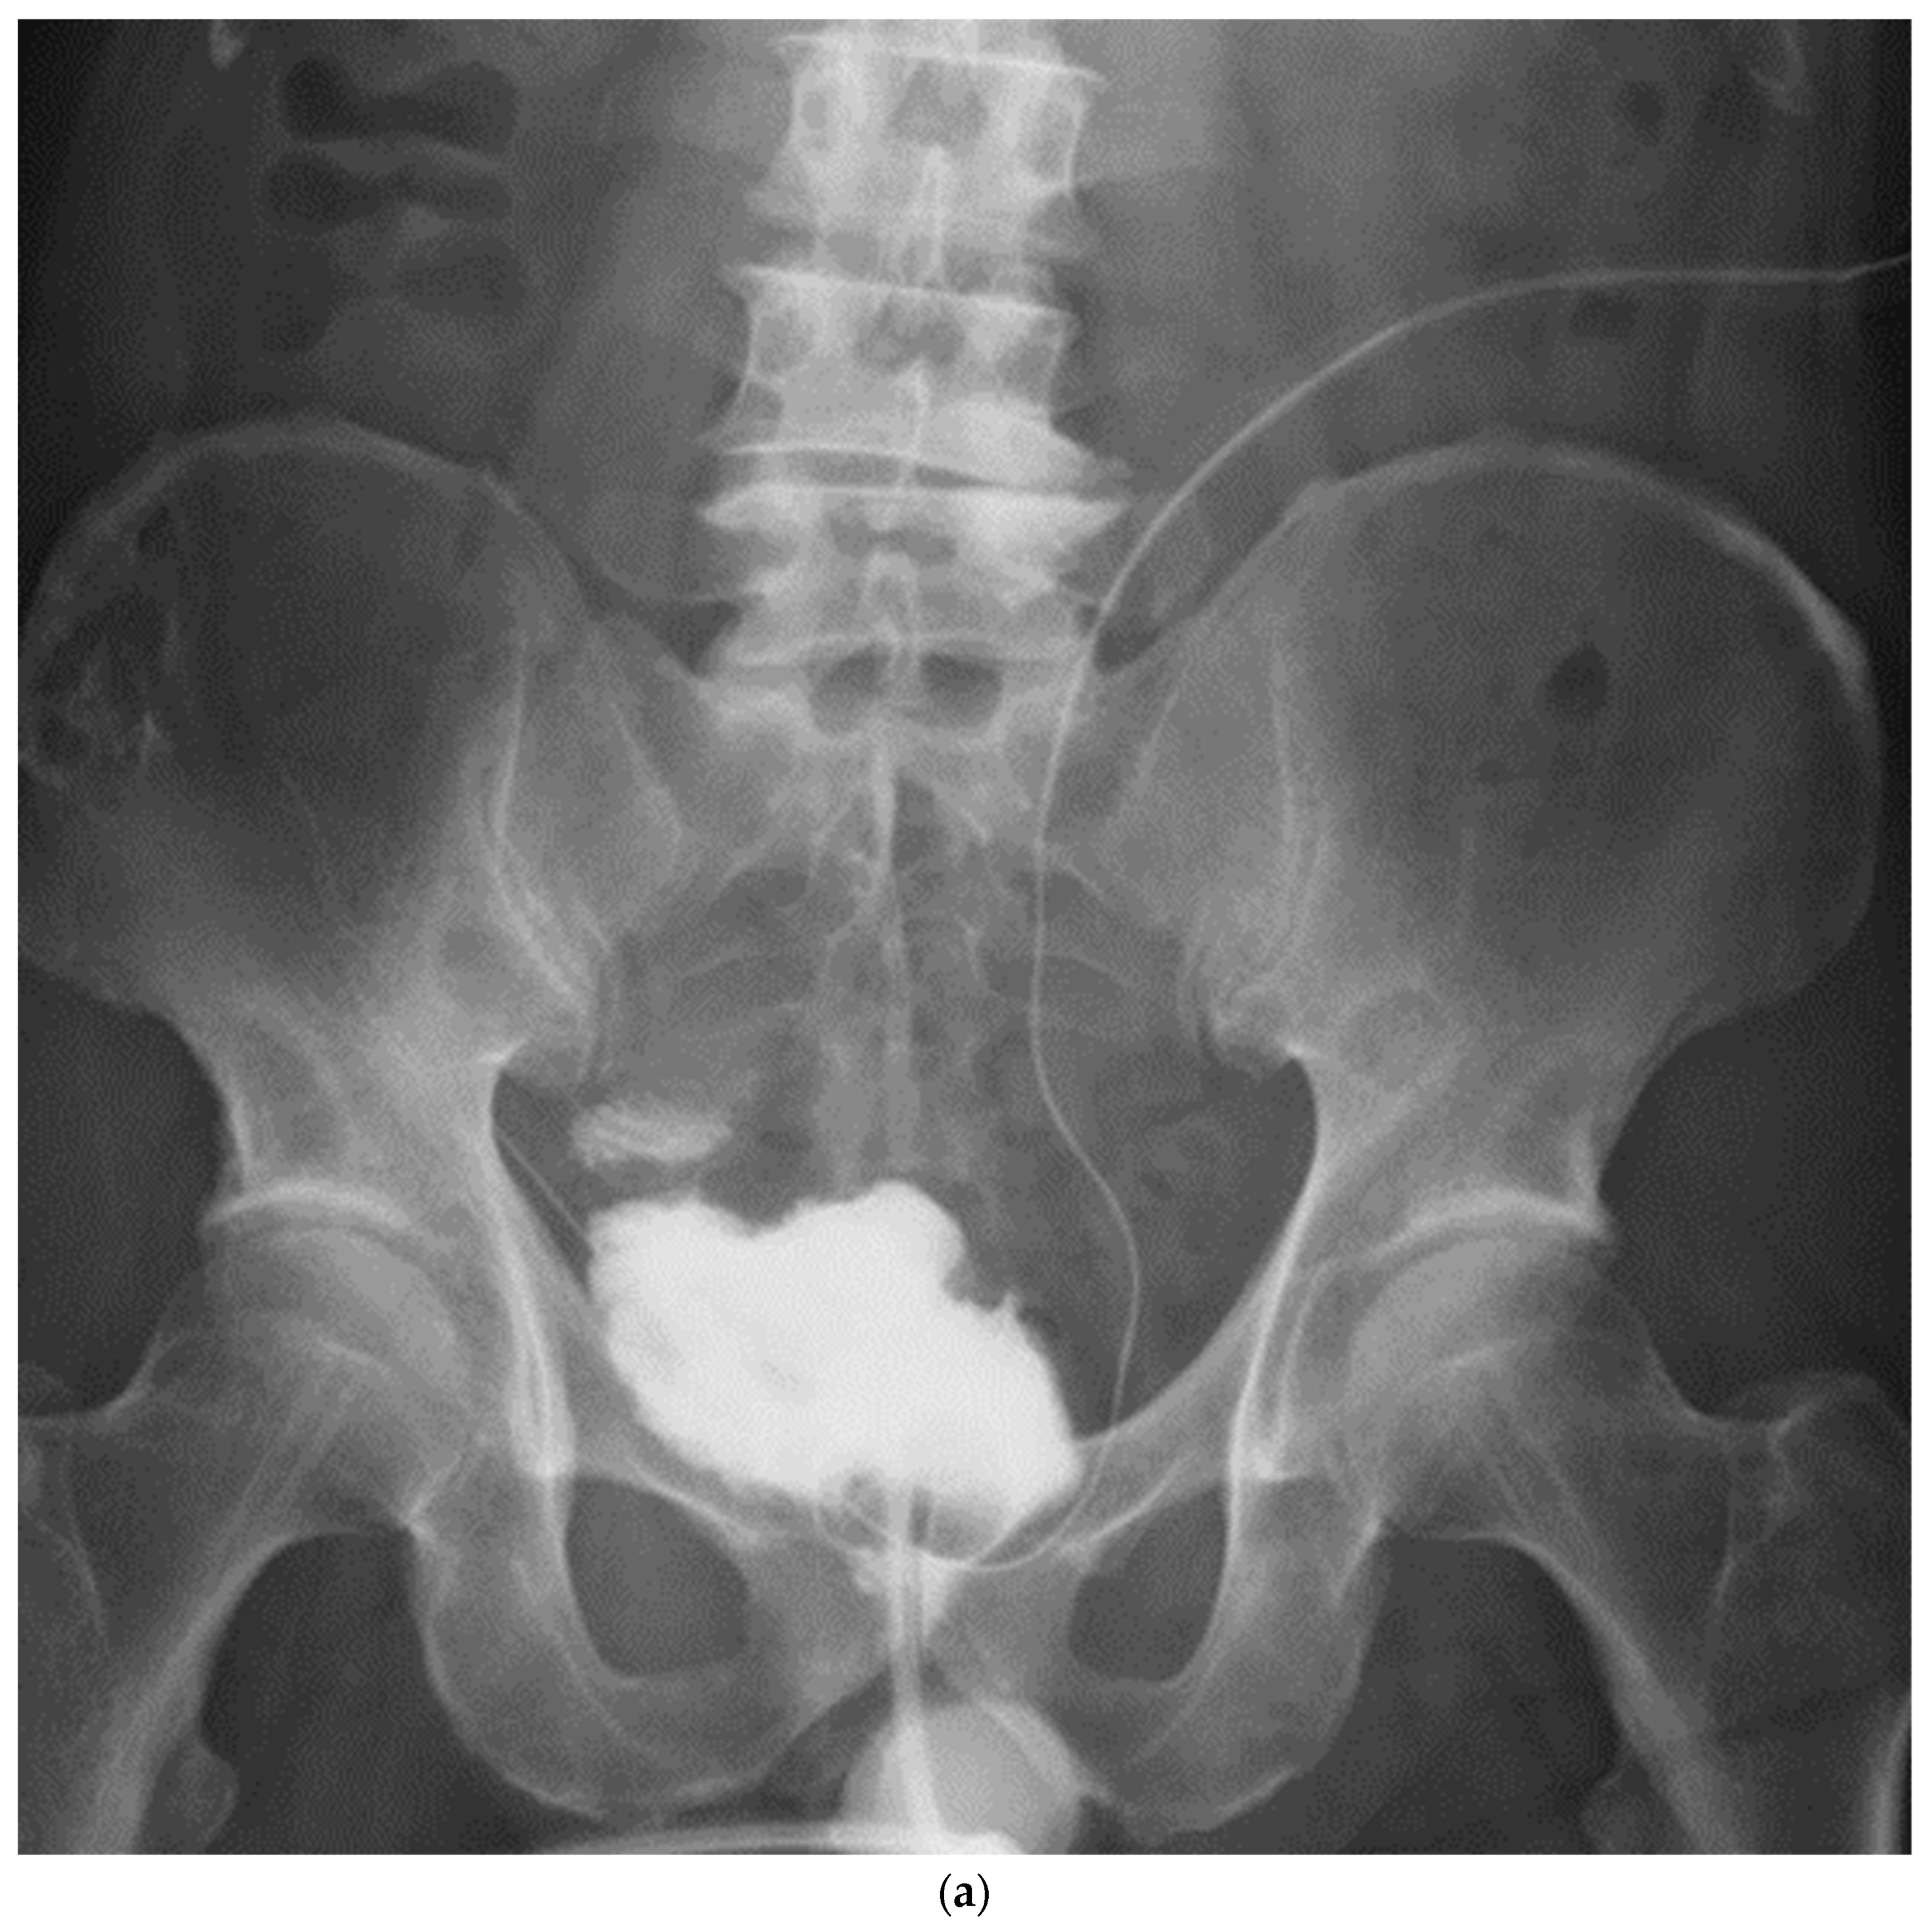

Patient demographics and variables are shown in Table 1. Most patients received neoadjuvant chemotherapy, and pT0 was achieved in two (20%) patients. Pathology confirmed organ-confined disease in seven (70%) patients and locally advanced disease in three (30%) patients. Nerve-sparing surgery was performed in three cases. Total operative time was 496 (418–815) min, and mean estimated blood loss was 524 (110–850) mL. No patients received intraoperative blood transfusions. In one patient, the ureteral stent was dislodged immediately after surgery, but no urine leakage was noted thereafter without reinserting. There were nine minor complications, as shown in Table 2. One patient had subileus but improved conservatively. One patient had urine leakage at the urethral anastomosis and a prolonged drain. Diarrhea was observed in two patients and improved with an oral antiflatulent agent. Vitamin B12 deficiency was observed in one patient, which was improved by oral supplementation. The urinary tract infection in one patient improved with an intravenous drip of antibiotics. No readmissions due to complications were observed. Continence was defined as zero or one safety pad, and postoperative early daytime continence was achieved in nine (90%) patients. Early nocturnal continence was achieved in eight (80%) patients. The three patients who underwent nerve-sparing RC were continent both during the daytime and nighttime. No patients required clean intermittent catheterization. There was no uretero-afferent limb stricture, urethro-enteric stricture, or decline in renal function. Figure 5 shows the cystography of the modified VIP NB two weeks after surgery.

Figure 5.

Cystography at 2 weeks after surgery. (a). Frontal view, (b). Oblique view.

It maintained the spherical shape established using our technique.